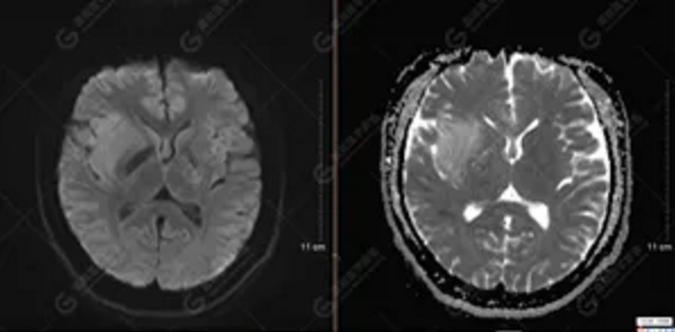

MR影像圖

【MRI平掃及增強(qiáng)檢查所見(jiàn)】右側(cè)額顳島葉、右側(cè)海馬及右側(cè)基底節(jié)區(qū)見(jiàn)一團(tuán)塊狀異常信號(hào)影,累及右側(cè)下丘腦及視交叉,大小約5.1cm×4.5cm×4.3cm,呈長(zhǎng)T1長(zhǎng)T2信號(hào),F(xiàn)LAIR序列呈等、稍高信號(hào),DWI序列呈稍高信號(hào),ADC圖高信號(hào),增強(qiáng)后無(wú)明顯強(qiáng)化;病灶周?chē)?jiàn)片狀長(zhǎng)T1長(zhǎng)T2水腫信號(hào)影,F(xiàn)LAIR序列呈高信號(hào),病灶內(nèi)見(jiàn)右側(cè)大腦中動(dòng)脈穿行。余腦實(shí)質(zhì)內(nèi)未見(jiàn)局灶性信號(hào)異常,增強(qiáng)后未見(jiàn)異常強(qiáng)化。右側(cè)側(cè)腦室輕度受壓,余腦室、腦池大小、形態(tài)均正常,中線(xiàn)結(jié)構(gòu)居中